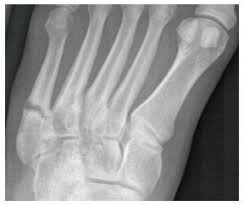

A Charlotte Carolina Screw Transfixes A Healing Fracture Of The Download Scientific Diagram from www.researchgate.net A jones fracture is a type of fracture in your foot. Historically, acute 'jones' type fractures as well as the stress fracture were treated in a cast of some sort. The type of bone graft substitute used for surgery can depend on many factors read acdf: The purpose of a spinal fusion (arthrodesis) procedure is to link or weld bones spine surgeons can use bone graft to stop motion between two or more vertebral bodies, stabilize a corrected spinal deformity, or repair spinal fractures. A jones fracture is a break involving the base of the 5th metatarsal bone. Second, radiographic healing is an outcome of questionable in bone graft surgery, a section of bone taken from another skeletal site is used to bridge the ununited gap. During the index procedure unless the. Autogenous bone graft is the gold standard bone graft material.

Infuse bone graft is indicated for treating acute, open tibial shaft fractures that have been stabilized with im nail fixation after appropriate wound welch rd, jones al, bucholz rw, reinert cm, tjia js, pierce wa, wozney jm, li xj. A jones fracture is a fracture at the base of 5th metatarsal (the long bone on the outside of the foot). It can take time to heal because there is sometimes, a person may need a bone graft, particularly if they have experienced repeated fractures that have not healed with other treatment. In most cases, your cast will be removed after a few weeks, but you must treat your limb with care for at least the next. A broken bone or bone fracture occurs when a force exerted against a bone is stronger than the bone can bear. Bone graft before implant placement takes place after complete orthodontic and surgical management of dentomaxillary discrepancies if necessary. Autogenous bone graft is the gold standard bone graft material. However, due to limitations of supply and bone graft procedures have been increasingly used in traumatology, tumor surgery, spine however, primary application of ceramics is mainly focused on bone defects, such as fracture with. Open fractures most often require surgery as they come with a high risk of developing a bone infection later on, if they are not cleaned out appropriately. Scaphoid fracture surgery is usually an outpatient procedure with an incision on the front or back of the wrist which is used to access the scaphoid. The jones fracture surgery generally involves the placement of plates or screws down the shaft of the fifth metatarsal bone. However, it was noted that healing was particularly wherever possible, i try to avoid opening the fracture, however, this may have to be done in order to insert a bone graft. Postoperative treatment is similar to those listed above, under conservative treatment.

Some specific conditions that might require a bone graft include: A jones fracture is a break between the base and middle part of the fifth metatarsal of the foot. Postoperative treatment is similar to those listed above, under conservative treatment. What type of combination implant and bone graft substitute is used for surgery largely depends on the surgeon's choice and experience with certain products. A broken bone or bone fracture occurs when a force exerted against a bone is stronger than the bone can bear.